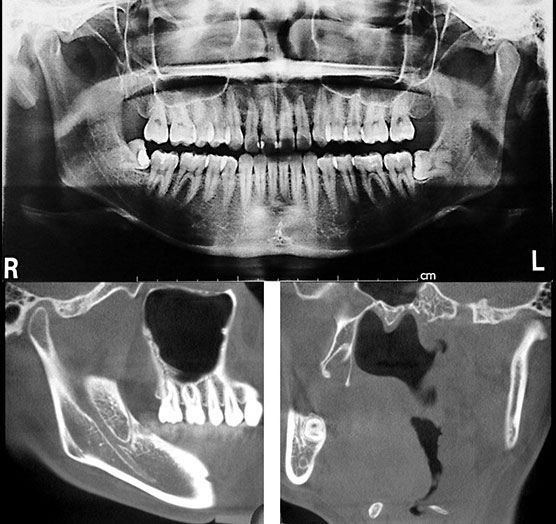

埋伏歯の適切な抜歯方法

日常の歯科臨床において、口腔領域の観血的処置の代表的な手技は、抜歯処置です。つまり安全に執り行うためには、小外科処置の基本的な知識と一連の手技が必要とされます。

また、患者様の全身的リスクや局所的リスク(臨床的・解剖学的リスクも含む)などを的確に診査診断を行い、当施設での処置の可否も含めた治療計画の判断を必要とすることもあります。

今回は、抜歯処置や小外科処置における、個々の症例の全身的リスク、局所的リスクを配慮した周術期管理をマスターしていただきます。

- ■埋伏智歯抜去処置における局所麻酔、切開、剝離、骨の切削、歯の分割、歯根の脱臼、掻爬、縫合の基本手技の確認。